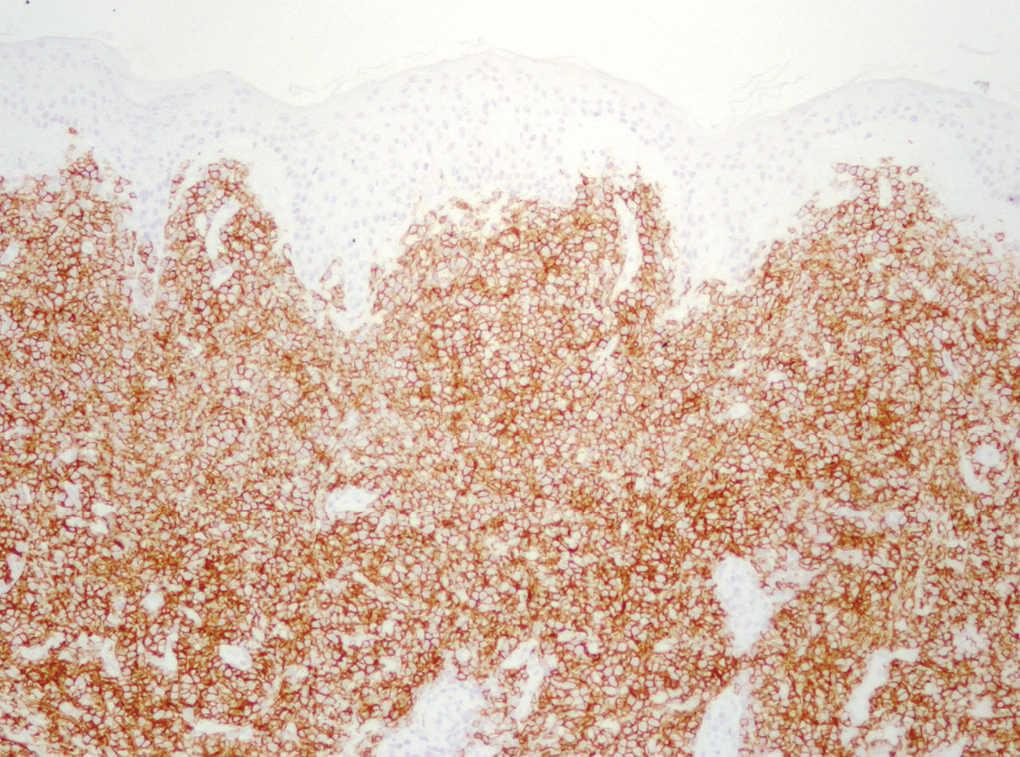

Dentro del infiltrado, densamente celular, predominaban los linfocitos de tamaño grande con núcleos redondeados, nucléolo excéntrico y cromatina finamente dispersa, que recordaban a los centroblastos; entre ellas se observaban frecuentes figuras de mitosis (fig. 3), así como una población de células de menor tamaño con núcleos más hipercromáticos y contornos más irregulares que corresponderían también a linfocitos aunque su número era menor (fig. 4). Se realizó tinción para CD20 que resultó intensamente positiva en la membrana de las células tumorales. El infiltrado resultó positivo para CD10 y bcl-2, y negativo para CD30 y bcl-6 (figs. 5 y 6).

Fig. 5.--Tinción intensamente positiva de las células tumorales para CD-20.